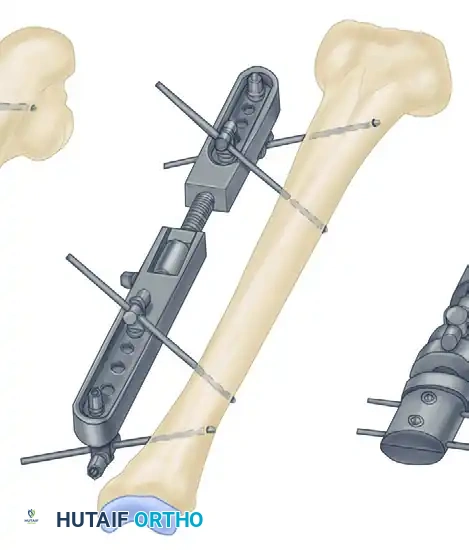

Biomechanics of External Fixation

Understanding the biomechanics of external fixation is critical for the orthopedic surgeon. The stability of the frame dictates the mechanical environment at the fracture site, which in turn influences the type of bone healing (primary vs. secondary).

Factors Influencing Frame Stiffness

The rigidity of an external fixator construct is determined by several modifiable variables:

* Pin Diameter: The stiffness of a half-pin is proportional to the fourth power of its radius ($r^4$). Increasing the pin diameter is the single most effective way to increase frame rigidity. However, pin diameter should not exceed one-third of the bone's diameter to prevent stress risers and subsequent iatrogenic fractures.

* Distance from Bone to Rod: The closer the longitudinal rod is to the bone, the stiffer the construct. The rod should be placed approximately 2 to 3 cm from the skin to allow for postoperative swelling while maximizing stability.

* Pin Spread: Increasing the distance between the two outermost pins in a single bone segment increases the stability of the construct.

* Number of Pins: Increasing the number of pins per segment increases stiffness, though the biomechanical advantage diminishes after three or four pins per segment.

* Number of Bars: Adding a second longitudinal bar (creating a stacked or double-bar construct) significantly increases stiffness, particularly in bending and torsion.

* Multiplanar Constructs: Placing pins in different planes (e.g., a delta frame or biplanar construct) dramatically increases torsional and bending rigidity compared to a uniplanar frame.